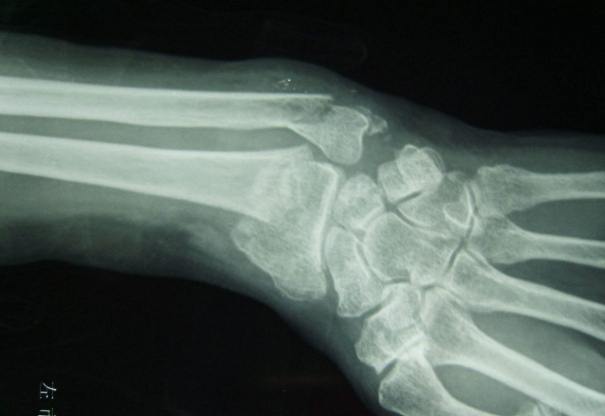

粉碎性骨折,簡單說就是骨頭碎成好幾塊,不像普通骨折只是裂開一條縫。這種骨折通常比較嚴重,可能是高能量撞擊造成的,比如車禍、高處墜落。骨頭碎片多了,癒合起來就麻煩,因為血液供應可能受影響,恢復自然慢。

有些人會問,粉碎性骨折和一般骨折有啥區別?我覺得最大差別在於穩定性。粉碎性骨折的骨頭碎片多,容易移位,治療上往往需要手術來固定。如果只是打石膏,可能不夠力,骨頭長歪的風險高。

根據骨折位置和嚴重程度,粉碎性骨折可以分幾種。比如開放性粉碎性骨折,就是骨頭刺出皮膚,這種更麻煩,因為有感染風險。閉合性就好一點,但恢復時間還是長。下表列出常見類型供參考:

| 開放性粉碎性骨折 | 骨頭穿出皮膚,感染風險高 | 四肢,如小腿、手臂 |

| 閉合性粉碎性骨折 | 皮膚完整,但內部骨頭碎裂 | 大腿、骨盆 |

| 關節內粉碎性骨折 | 影響關節面,可能導致關節炎 | 膝蓋、腳踝 |